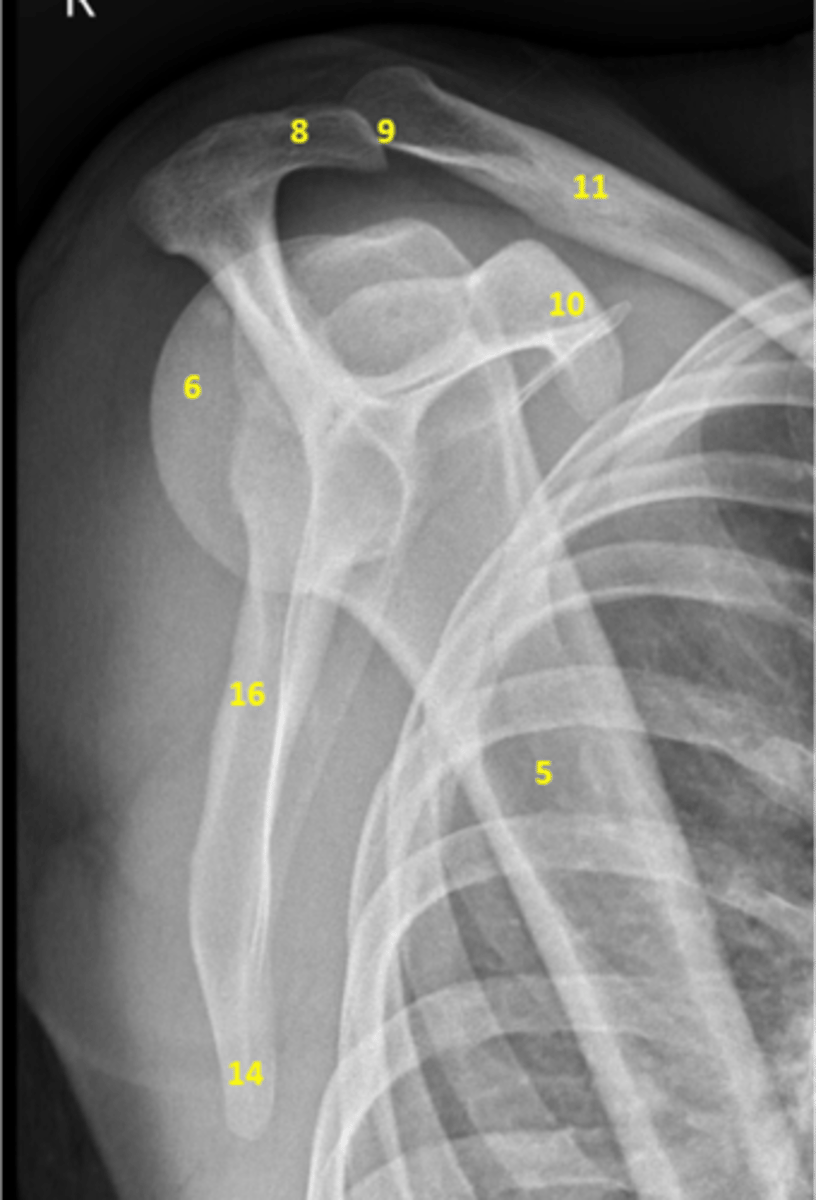

View: Y-view

5. Humeral shaft

6. Head of the humerus

8. Acromion

9. Distal end of the clavicle

10. Coracoid process

11. Clavicular shaft

14. Inferior angle of the scapula

16. Medial border of the scapula

Label this image. Bonus: which type of view is this?